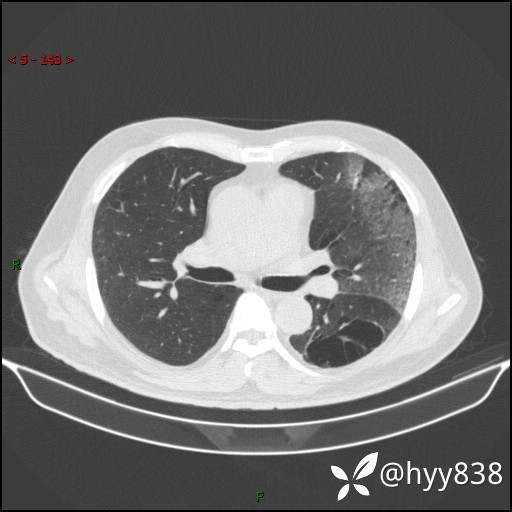

一周前胸部CT